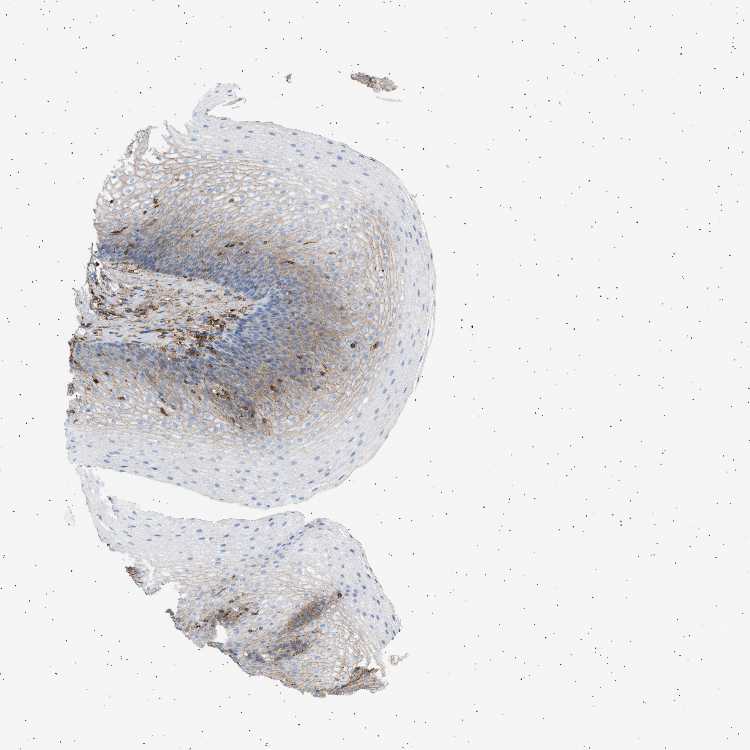

ESOPHAGUS - Antibody stainingi

Antibody staining in the annotated cell types in the current human tissue is reported as not detected, low, medium, or high, based on conventional immunohistochemistry profiling in selected tissues. This score is based on the combination of the staining intensity and fraction of stained cells.

Each image is clickable and will lead to virtual microscopy that enables deeper exploration of all samples and also displays staining intensity scores, fraction scores and subcellular localization as well as patient and tissue information for each sample.

Antibody HPA060604Antibody CAB016072

Squamous epithelial cells Not detectedLow